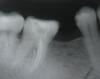

zhenya_88 Опубликовано 10 апреля, 2011 Автор Поделиться Опубликовано 10 апреля, 2011 (изменено) снимок пациента, о котором говорилось в начале. (в дистальном стекловолокно). апекслокатор везде просигнализировал апекс, а на рентгене вышло вот что...причем такое впечатление что в мезиально-язычном какойто обломок, хотя в действительности я ничего не ломала, инструменты новенькие взяла... что скажете про дистальный? п.с. в процессе пломбировки делала снимки с мастер штифтами, на которых было видно недопломбировку, вынула штифты, повторная обработка и доразработка каналов, мыла-перемыла, апекслокатором проверила длину, все было отлично, запломбировала... потом в одно из последующих посещений (когда ставила стекловолокно) решила сделать еще один снимок для себя чтоб посмотреть... это он....жду Ваши мнения по поводу работы... Изменено 10 апреля, 2011 пользователем zhenya_88 Ссылка на комментарий

ger_berra Опубликовано 10 апреля, 2011 Поделиться Опубликовано 10 апреля, 2011 (изменено) снимок пациента, о котором говорилось в начале. (в дистальном стекловолокно). апекслокатор везде просигнализировал апекс, а на рентгене вышло вот что...причем такое впечатление что в мезиально-язычном какойто обломок, хотя в действительности я ничего не ломала, инструменты новенькие взяла... что скажете про дистальный? п.с. в процессе пломбировки делала снимки с мастер штифтами, на которых было видно недопломбировку, вынула штифты, повторная обработка и доразработка каналов, мыла-перемыла, апекслокатором проверила длину, все было отлично, запломбировала... Какой именно показатель АЛ был(0.5,0.0 ..),мерили в сухом,мокром канале?По-моему,недолёт.Если латералите,то вероятнее всего это пора между гуттой и силлером.А показываете 47,вместо 37 Изменено 10 апреля, 2011 пользователем ger_berra Ссылка на комментарий

zhenya_88 Опубликовано 10 апреля, 2011 Автор Поделиться Опубликовано 10 апреля, 2011 (изменено) Какой именно показатель АЛ был(0.5,0.0 ..),мерили в сухом,мокром канале?По-моему,недолёт.Если латералите,то вероятнее всего это пора между гуттой и силлером.А показываете 47,вместо 37 мерила в сухом. это 37 (просто рентген снимок не цифровой, я его сфоткала, видимо наоборот, переволновалась((((показатель был о.о. (apex) в дист. и мез.щеч., в мез.яз. - 0.2 Вы считаете, недолет во всех каналах? Изменено 10 апреля, 2011 пользователем zhenya_88 Ссылка на комментарий

ger_berra Опубликовано 10 апреля, 2011 Поделиться Опубликовано 10 апреля, 2011 мерила в сухом. это 37 (просто рентген снимок не цифровой, я его сфоткала, видимо наоборот, переволновалась((((показатель был о.о. (apex) в дист. и мез.щеч., в мез.яз. - 0.2 Вы считаете, недолет во всех каналах?Да,если по АЛ 0.0и 0.2http://s007.radikal.ru/i300/1104/d2/941c2796969c.jpgХорошо бы ещё снимок в прямой проекции,тогда можно точнее сказать.Измерять лучше во влажном канале.Я после ирригации вставляю инструмент и сдуваю пустером лишнюю влагу(только "прям туда" дуть не надо ).Или с лубрикантом. Ссылка на комментарий